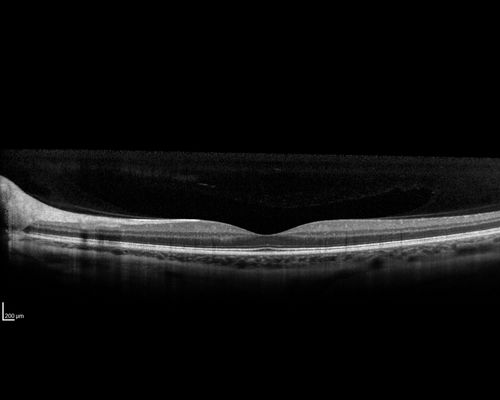

31 year old male with anaplastic astrocytoma on chemotherapy with mild vision loss in the right eye.  LP did not reveal organism.  He was placed on a trial of anti-fungal medications and lost to follow-up